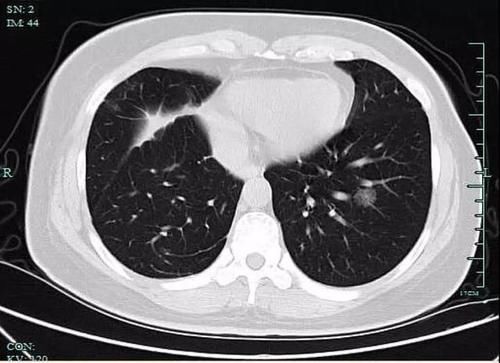

但也许是因为太拼了,章女士忽略了自己的身体变化。前年7月,章女士开始咳嗽,“是那种干咳,也没有流鼻涕没有喉咙痛,应该不是感冒。”她回忆,因为咳得实在难受就想去社区医院配点药,但医生建议她最好去大医院检查一下。章女士便来到浙大一院就诊并预约了检查,拿到体检结果那一刻她却直冒汗,“CT结果说我两侧的肺上都有磨玻璃小结节,右肺上叶的已经有1厘米大了,首先考虑是肺癌,我吓都吓‘死’了。”

经过评估,章女士右肺情况符合手术指征,随后接受了微创肺癌根治术,术后病理报告提示为肺周围型中分化浸润性腺癌。2019年12月,在一次常规复查中,章女士左肺下叶的结节也恶变了,考虑可能是肺癌,经医生评估后再次接受了微创肺癌根治术,目前已经康复出院。